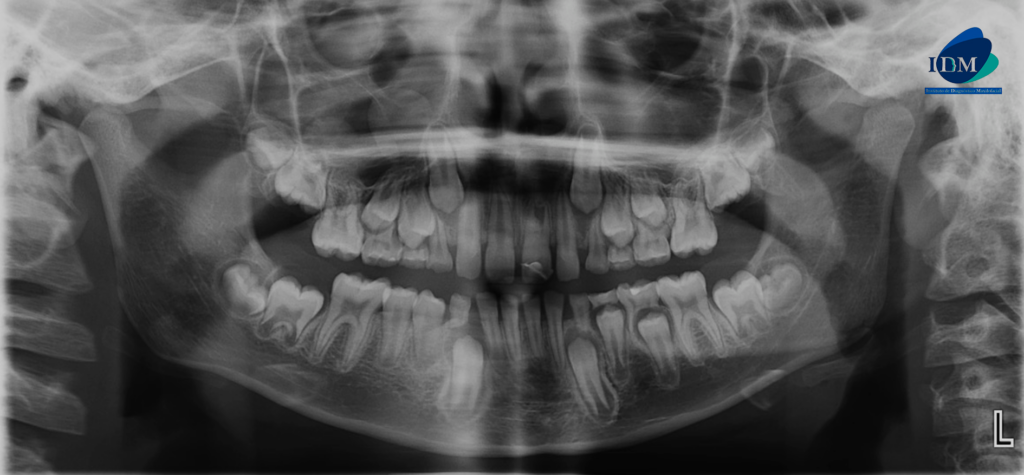

En la radiografía panorámica (Figura 1), se observa pieza 21 con material restaurador coronal, obliteración parcial cámara y conducto radicular.

Radiografia Panorámica